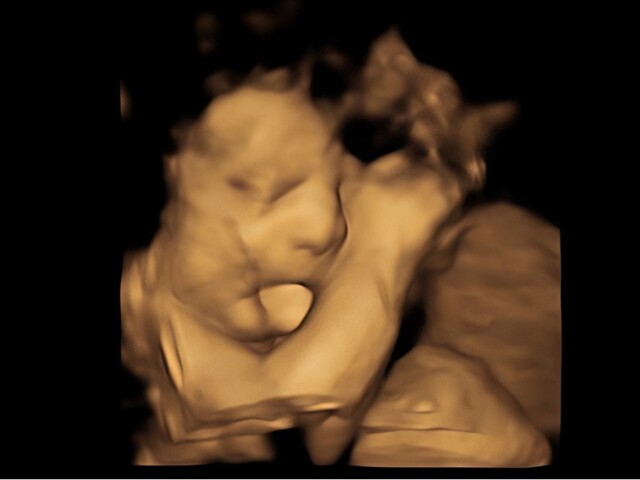

Nữ sinh chụp bụng bầu 7 tháng phẳng lỳ, láng mịn, ảnh siêu âm đứa trẻ khiến nhiều người hoang mang

Cô gái trẻ bị nghi ngờ mang bầu giả vì chiếc bụng khó tin.